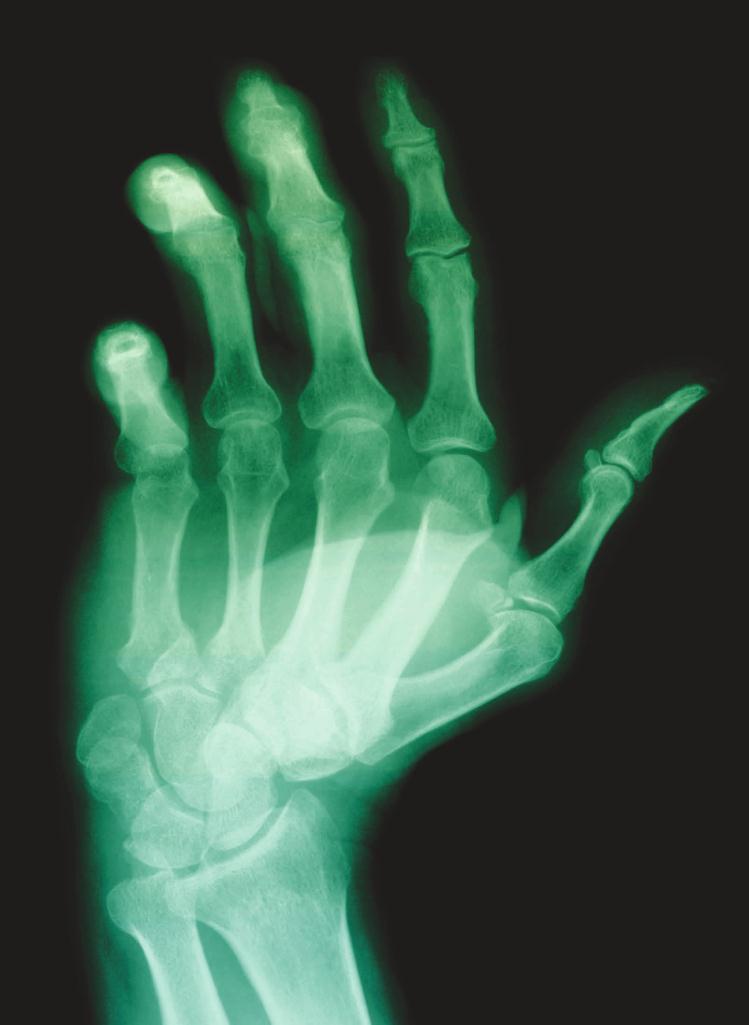

“To diagnose rheumatoid arthritis, blood work will usually be

recommended; however, a rheumatoid hand can be easily identified by

appearance. While surgery is always a last option, replacements may

be necessary based on the severity of the deformities, especially if the

patient is not responding to oral treatments.” —Hussein Turki, MD